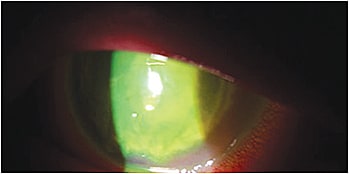

Note the large stromal ring infiltrate with an overlying epithelial defect and stromal white blood cell infiltration in this patient.

Exam revealed severe bilateral corneal ulcers and keratitis — the worst cases I’d ever seen — and uncorrected vision that was light perception OU.

Based on her history and clinical presentation, I suspected the patient had Acanthamoeba keratitis (AK) OU.